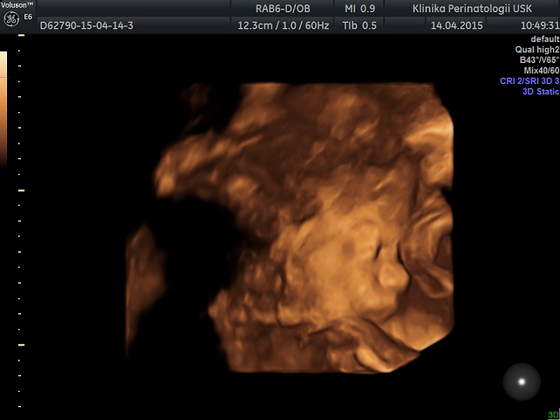

Ja też dziś miałam usg ale to młodzi doktorzy robili, więc bez szczegółów... mieli problem ze złapaniem czegokolwiek ale kawałek twarzyczki widać, szkoda tylko że nóżek nie chciał rozłożyć żeby pisiorka pokazać

a to Tymonek 24t 4d